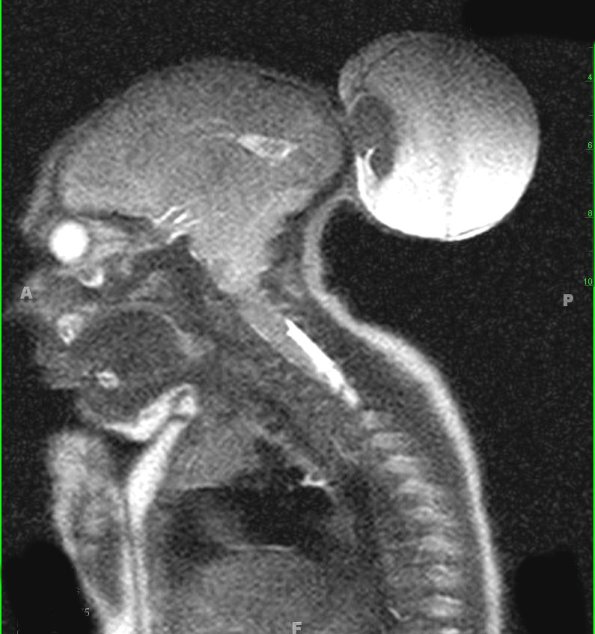

Several views of the encephalocele with T1-weighted contrast applied axial scan (9A1) and T2-weighted images (9A2-4) which show a complement of herniated brain tissue.